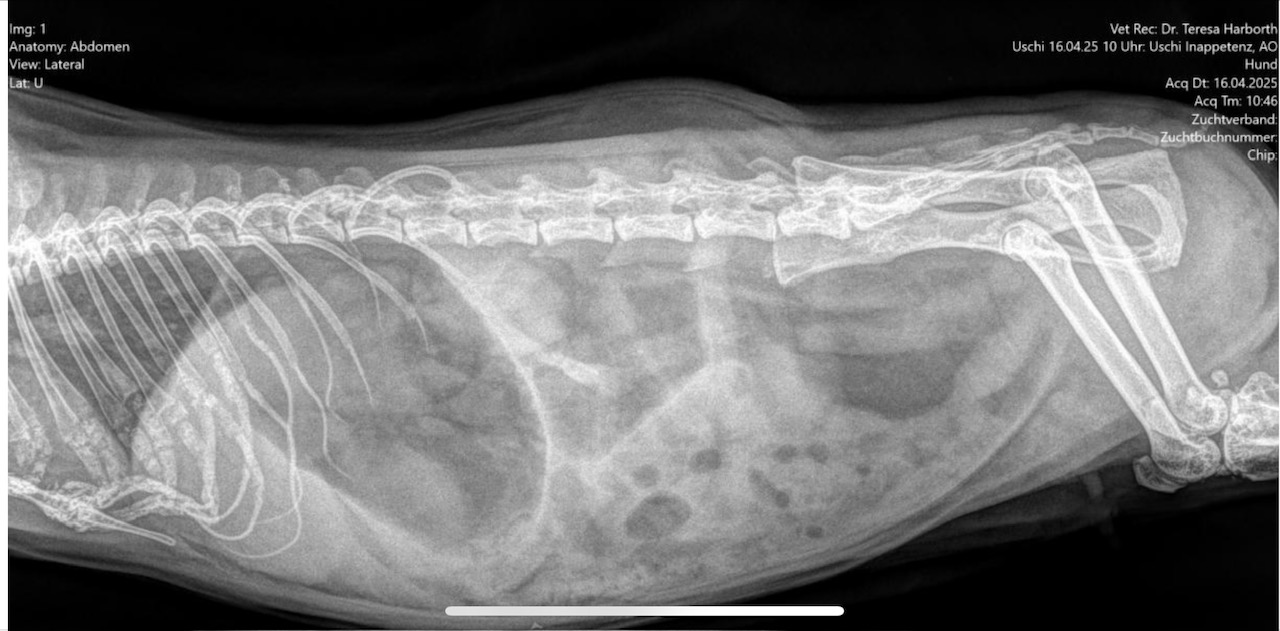

Uschi ist immer noch aufgegast. Das ins Gleichgewicht zu bringen ist das vordringliche Ziel bis morgen. Die Zähne scheinen augenscheinlich erstmal in Ordnung zu sein, doch es besteht die Befürchtung, dass mit dem Kiefer oder/und den Zahnwurzeln etwas nicht stimmen könnte. Dazu soll ein Kopf-CT gemacht werden. Das würde erst nach Ostern durchgeführt werden. Ob Uschi erstmal nur bis morgen in Hannover bleibt und das CT dann in "unserer" Tierklinik in Posthausen durchgeführt wird oder ob sie bis Dienstag in der TiHo bleibt, soll sich morgen zeigen. Das Röntgenbild ergab leider auch noch einen Hinweis, dass im Bereich Niere oder Eierstock ein weiteres Problem bestehen könnte. Dieses sind die Röntgenbilder vom 1. Befund.

meerschweinchenforum.eu/a/attachment/4344/